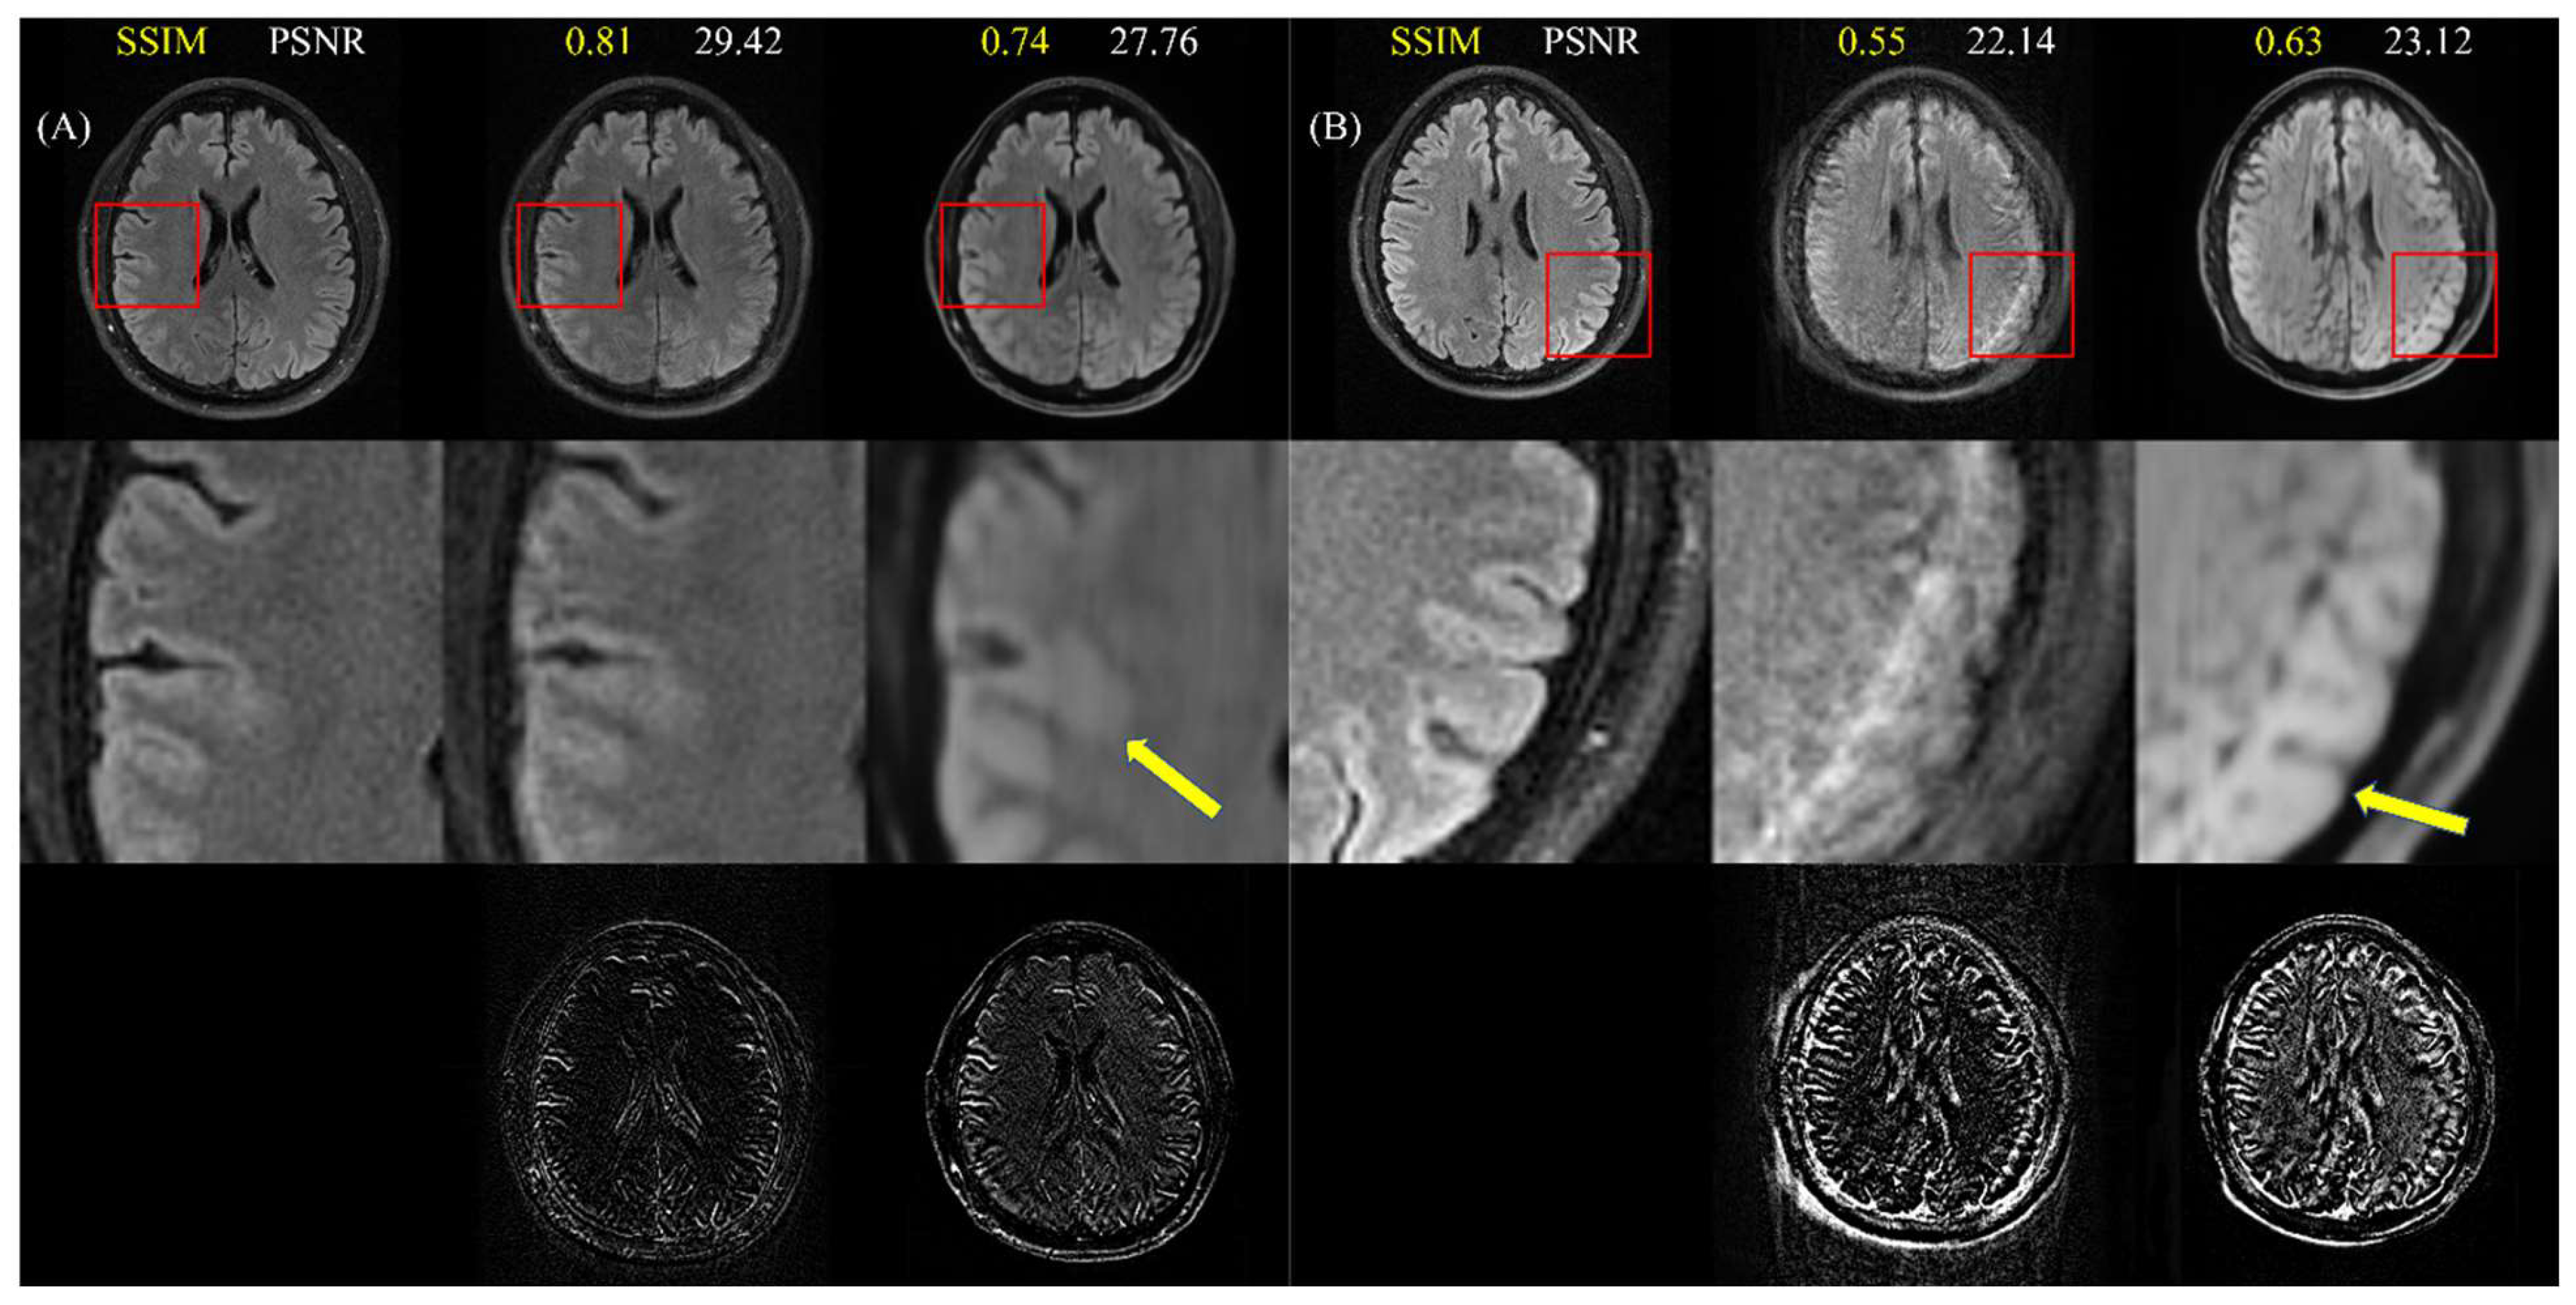

4.5. Images with Real (Non-Simulated) Motion